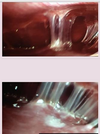

PID

104

PID COMPLICATION

Fitz hugh curtis

endocervical polyps

107

Endocervical polyp histo

108

cervical intraepithelial neoplasia